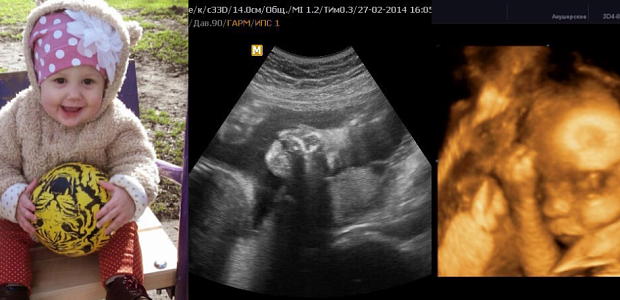

Узи плода в 3D-4D

4 000  Р

В сети клиник «Здоровье», в офисе на Советском, 24, будущие мамы могут сделать 3D и 4D УЗИ. Эта процедура является безопасной и информативной. При этом беременные женщины получат фото и видео будущего ребёнка на цифровой носитель.

Трехмерная реконструкция позволяет более чётко увидеть пороки лица, головы, визуализировать грыжевые выпячивания спинного мозга, передней брюшной стенки, пороки конечностей и аномалии позвоночника.